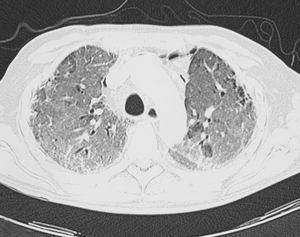

Al ingresar presentaba una presión arterial de 110/60 mmHg, frecuencia cardíaca de 120 lat/min, taquipnea intensa (> 40 respiraciones/min) y saturación del 80% con oxígeno por Ventimask al 50%. Se realizó una nueva TACAR que evidenció áreas extensas y bilaterales de opacidades en vidrio deslustrado, superpuestas al patrón crónico de engrosamiento intersticial y panalización que presentaba previamente (fig. 2). Se inició tratamiento empírico con esteroides a dosis de 2 mg/kg/día, así como levofloxacino y cotrimoxazol. Ante la ausencia de mejoría clínica y gasométrica a las 24 h (saturación arterial de oxígeno < 80% respirando aire en reservorio de 10 l), se decidió su ingreso en la unidad de cuidados intensivos para la realización de catéter telescopado y lavado broncoalveolar (BAL). Se enviaron únicamente muestras para microbiología y la exploración se interrumpió por intensa desaturación y mala tolerancia al BAL. El paciente permaneció 5 días en la unidad de cuidados intensivos, donde se retiró el tratamiento con cotrimoxazol y se añadió azatioprina a dosis iniciales de 1 mg/kg/día, sin que precisar soporte inotrópico ni ventilatorio. Ingresó de nuevo en planta de hospitalización en un estado clínico y gasométrico similar, persistiendo la insuficiencia respiratoria refractaria y la taquipnea intensa.

Figura 2. En la imagen se pueden apreciar áreas extensas en vidrio deslustrado, bilaterales, superpuestas a imágenes de engrosamiento septal y subpleural.